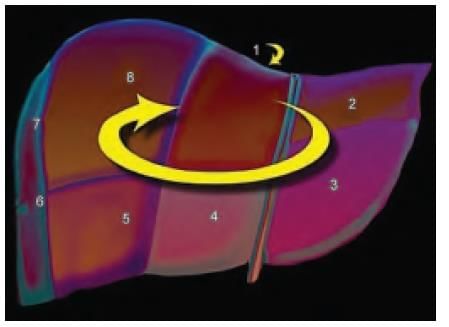

Liver is divided into eight segments according to Couinaud’s classification based upon. (AIIMS May 2019)

In CT scan of liver, identify the arrow marked segment: (INI-CET Nov 2022)